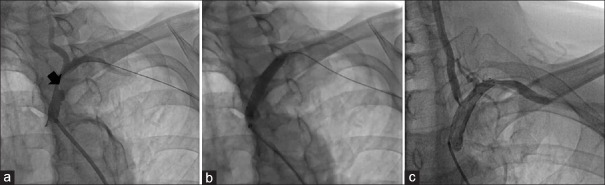

Successful subclavian artery stenting in a patient with subclavian steal syndrome associated with contralateral vertebral artery hypoplasia.

锁骨下窃断综合征伴对侧椎动脉发育不全患者的锁骨下动脉支架置入术成功。